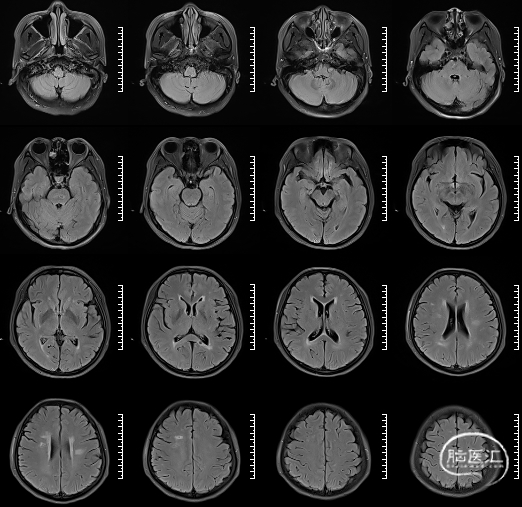

![]()

左侧脑室旁亚急性期-慢性期脑梗死

右侧椎动脉局部梭形扩张,管壁增厚